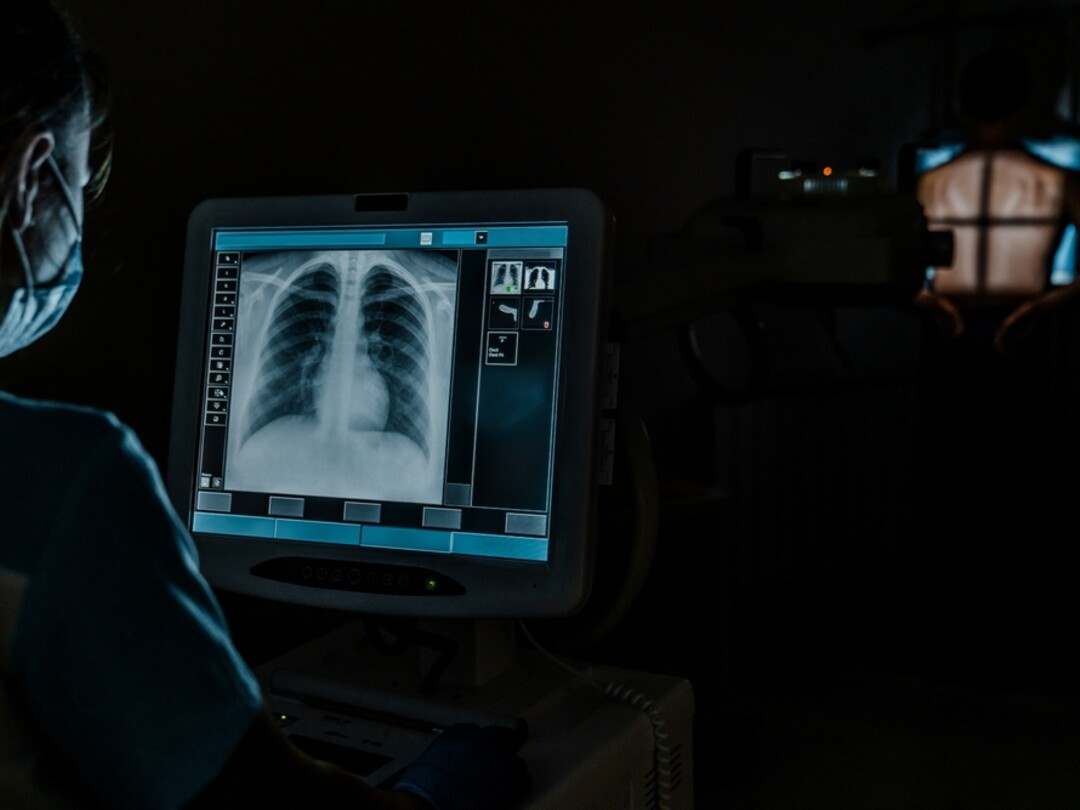

Bij patiënten met niet-traumatische thoracale klachten op de SEH wordt standaard een X-thorax verricht. ‘Ultra-low-dose’ CT-thorax heeft echter een grotere diagnostische accuratesse bij een vergelijkbare stralingsdosis. Welke van deze twee onderzoeken heeft de voorkeur?

‘Ultra-low-dose’ CT-thorax (ULDCT) heeft een grotere diagnostische accuratesse dan X-thorax bij een vergelijkbare stralingsdosis. Dat maakt ULDCT een aantrekkelijk alternatief op de SEH.

We beoordeelden de impact op gezondheidsuitkomsten van het vervangen van X-thorax door ULDCT bij patiënten met niet-traumatische thoracale klachten op de SEH.

ULDCT is in vergelijking met X-thorax niet-inferieur op het gebied van fysiek functioneren, met minimale verschillen in ziekenhuisopnames, opnameduur, mortaliteit en economische impact. ULDCT gaf meer nevenbevindingen, maar in de 28 dagen na de ULDCT was minder aanvullende beeldvorming nodig dan bij X-thorax. Pneumonie werd vaker correct gediagnosticeerd met ULDCT. Bij patiënten met een atypische presentatie van pneumonie presteerde ULDCT beter dan de X-thorax.

Onze studie toont aan dat er geen reden is om bij SEH-patiënten met niet-traumatische thoracale klachten de X-thorax door ULDCT te vervangen. Bij kwetsbare patiënten bevelen wij aan om te overwegen eerst ULDCT te verrichten in plaats van een X-thorax.